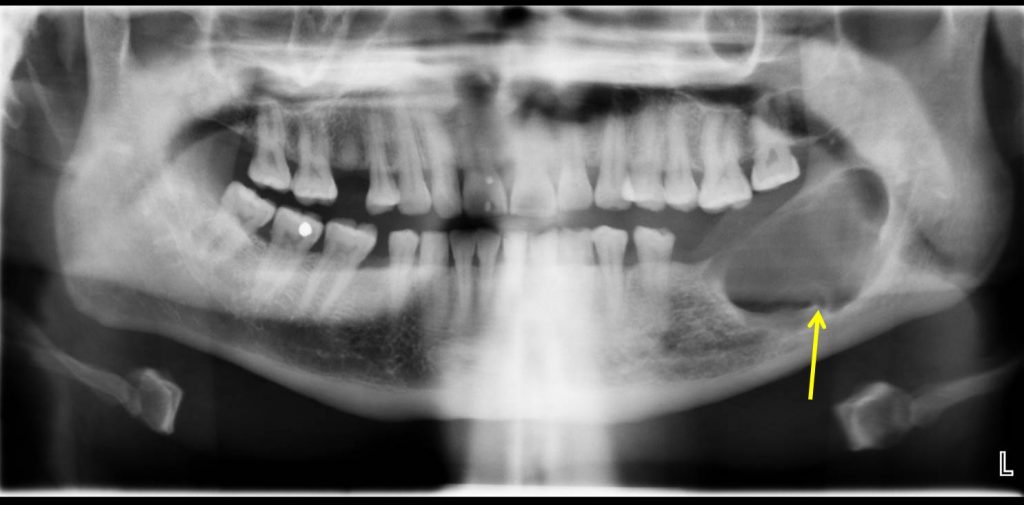

Ameloblastoma X Ray Can Ameloblastoma Be Fatal  Ameloblastomas are rare, odontogenic tumors derived from odontogenic ectoderm. Ameloblastomas represent about 1% of all jaw tumors, but they. Although extremely rare, ameloblastoma can be (or become) malignant. Ameloblastoma is a rare head and neck tumor with an estimated annual incidence of 0.5 per million population [1, 2]. Out of 15 patients nine were males. Ameloblastoma is a common but. Can Ameloblastoma Be Fatal.